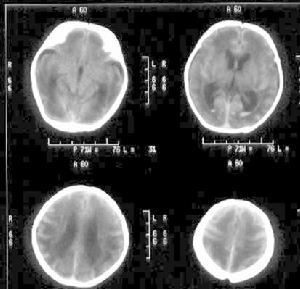

新生兒缺氧缺血腦病1. 缺氧缺血腦病 多發生在早產兒和窒息兒,顱內超聲檢查有助於診斷。